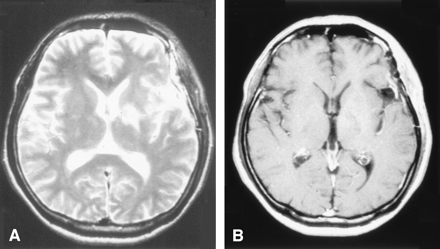

Under the diagnosis of brain tumor, glycerol was administered to prevent the progression of cerebral edema, after which the neurologic symptoms promptly improved. Cerebral angiography showed neither tumor stains nor other vascular abnormalities. To establish the final diagnosis, a craniotomic biopsy was performed on hospital day 14. The histopathologic findings excluded neoplastic lesions, showing only mild reactive gliosis without inflammatory cell infiltration (Fig 2). On hospital day 23, the patient was treated with high-dose methylprednisolone (m-PSL), a 3-day intravenous infusion of m-PSL with dose of 1000 mg/day, followed by an oral administration of prednisolone with dose of 30 mg/day. As the result, a remarkable improvement of the neurologic symptoms was achieved. Also the shrinkage of the cerebral lesion was noted on the MR images (Figs 3, 4).

The follow-up MR images (second time) at about a month after the start of steroid therapy. The lesion had a more reduction in size compared with previous images.

A, T2-weighted MR images

B, Postcontrast T1-weighted images